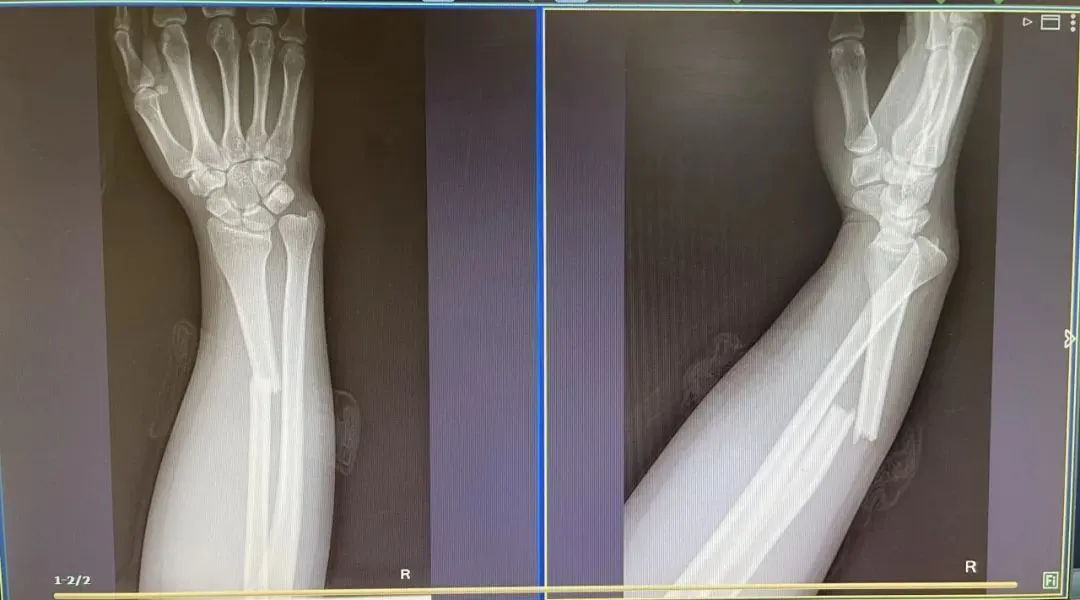

摔伤骨折……

类似意外非个例

近年来儿童骑坐行李箱

意外受伤的案件屡有发生

刘女士手臂也骨折了